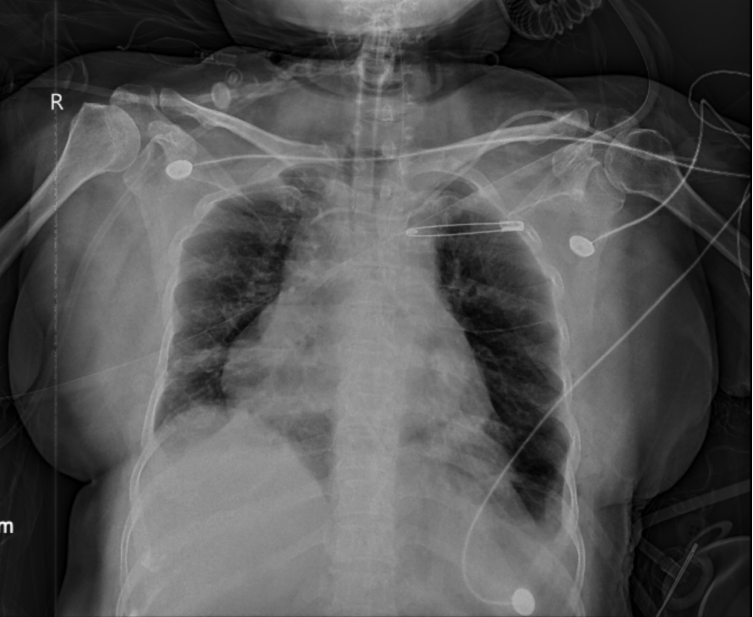

手术很成功——术后复查CT显示,左下肺明显复张,被压缩的肺终于重新“打开”了。

上海哪里买呼吸机好为何肺炎治好了,呼吸机却始终撤不掉?61岁阿姨ICU救治数月,左肺几乎无法正常工作,多学科协作如何“微创”破局?_https://www.jmylbn.com_新闻资讯_第2张

【术后胸片:左侧膈肌位置恢复,左下肺复张】

但康复之路并非一帆风顺。术后陈阿姨的肺部感染一度加重,ICU团队根据微生物培养结果及时调整了抗生素方案。脱机训练也经历了反复:术后一周开始尝试脱机,但期间出现了低氧和二氧化碳潴留,需要接回呼吸机后再次尝试。康复是个反复的过程,尤其对于陈阿姨这样长期卧床、合并多种复杂问题的患者。